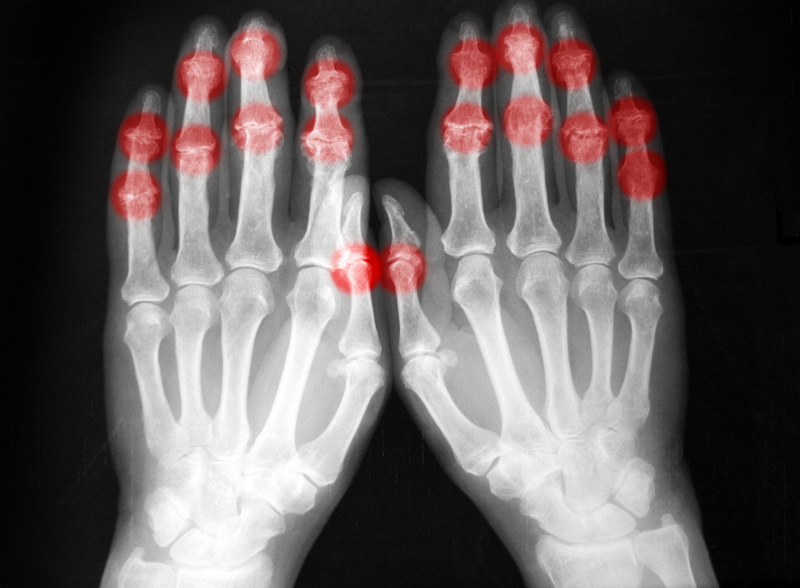

With only 5,000 radiographers serving a population of 200 million, Nigeria has a radiographer-to-population ratio of 1:40,000, which is considered deeply inadequate. The country also lacks sufficient medical imaging equipment, with only 183 CT machines and 58 MRI machines available as of 2018 and 2016, respectively. Jayeoba cited human error, lack of standardised working environments, and poor remuneration as specific challenges facing radiographers.